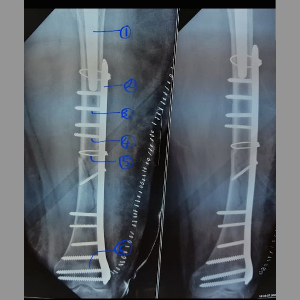

Peri prosthetic fracture

Makes readers familiar with Vancouver classification of peri prosthetic fractures.

Peri prosthetic fracture

Makes readers familiar with Vancouver classification of peri prosthetic fractures.